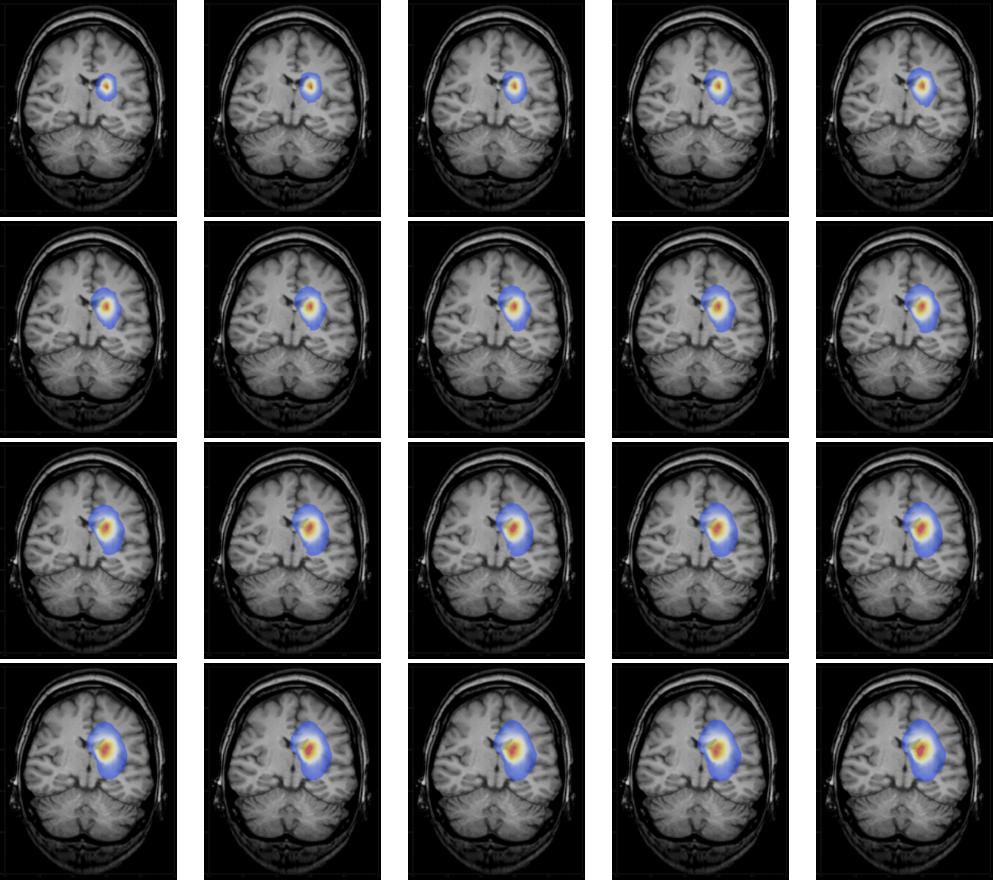

Brain tumor Cell Density Estimation From Multi-modal MR ...

Brain tumor cell density estimation from multi-modal MR images based on a synthetic tumor growth model E. Geremia 1, B. H. Menze;2 3, M. Prastawa4, M.- ... Return Doc

Brain Tumor Growth And Volume Detection By Ellipsoid-Diameter ...

The tumor cells that lie in the affected region from day by day report from MRI data. Here the Experimental result (graph) shows the growth of brain tumor cells. ... Read More